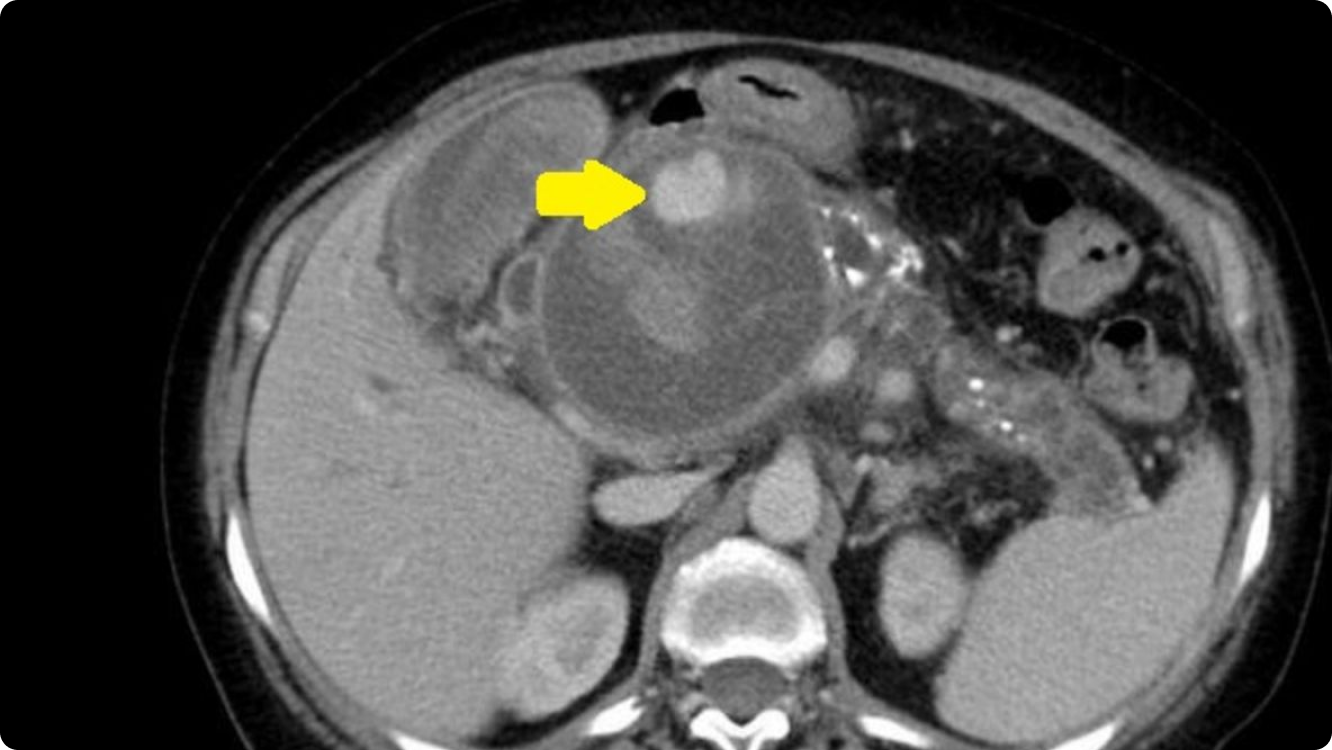

A well-defined oval cyst isseen abutting the pancreatic body and tail, suggestive of a pancreatic pseudocyst. The pancreatic duct is minimally prominent. Thecyst is seen anteriorly abutting the stomach wall with resultant diffuse oedematousthickening of the walls of the stomach.A few ill-defined hyperdensitiesare seen within the cyst, suggestive of chronic hemorrhages/ sludge